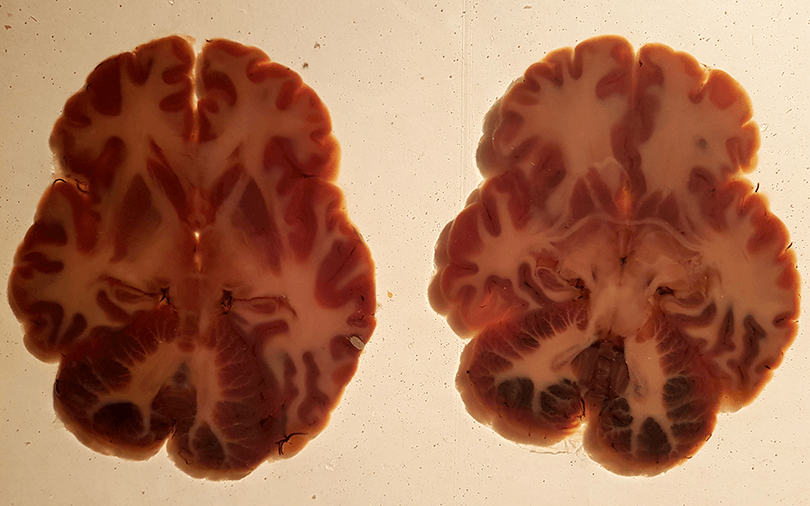

Consider the brain, the seat of consciousness, a miracle of evolution more complex than the computing powers of the world combined, with all the appearance of fungal meat. Branching out like roots are our nerves, ever finer as they reach the extremities; the feet which moves us and the hands with which our greatest works are wrought.